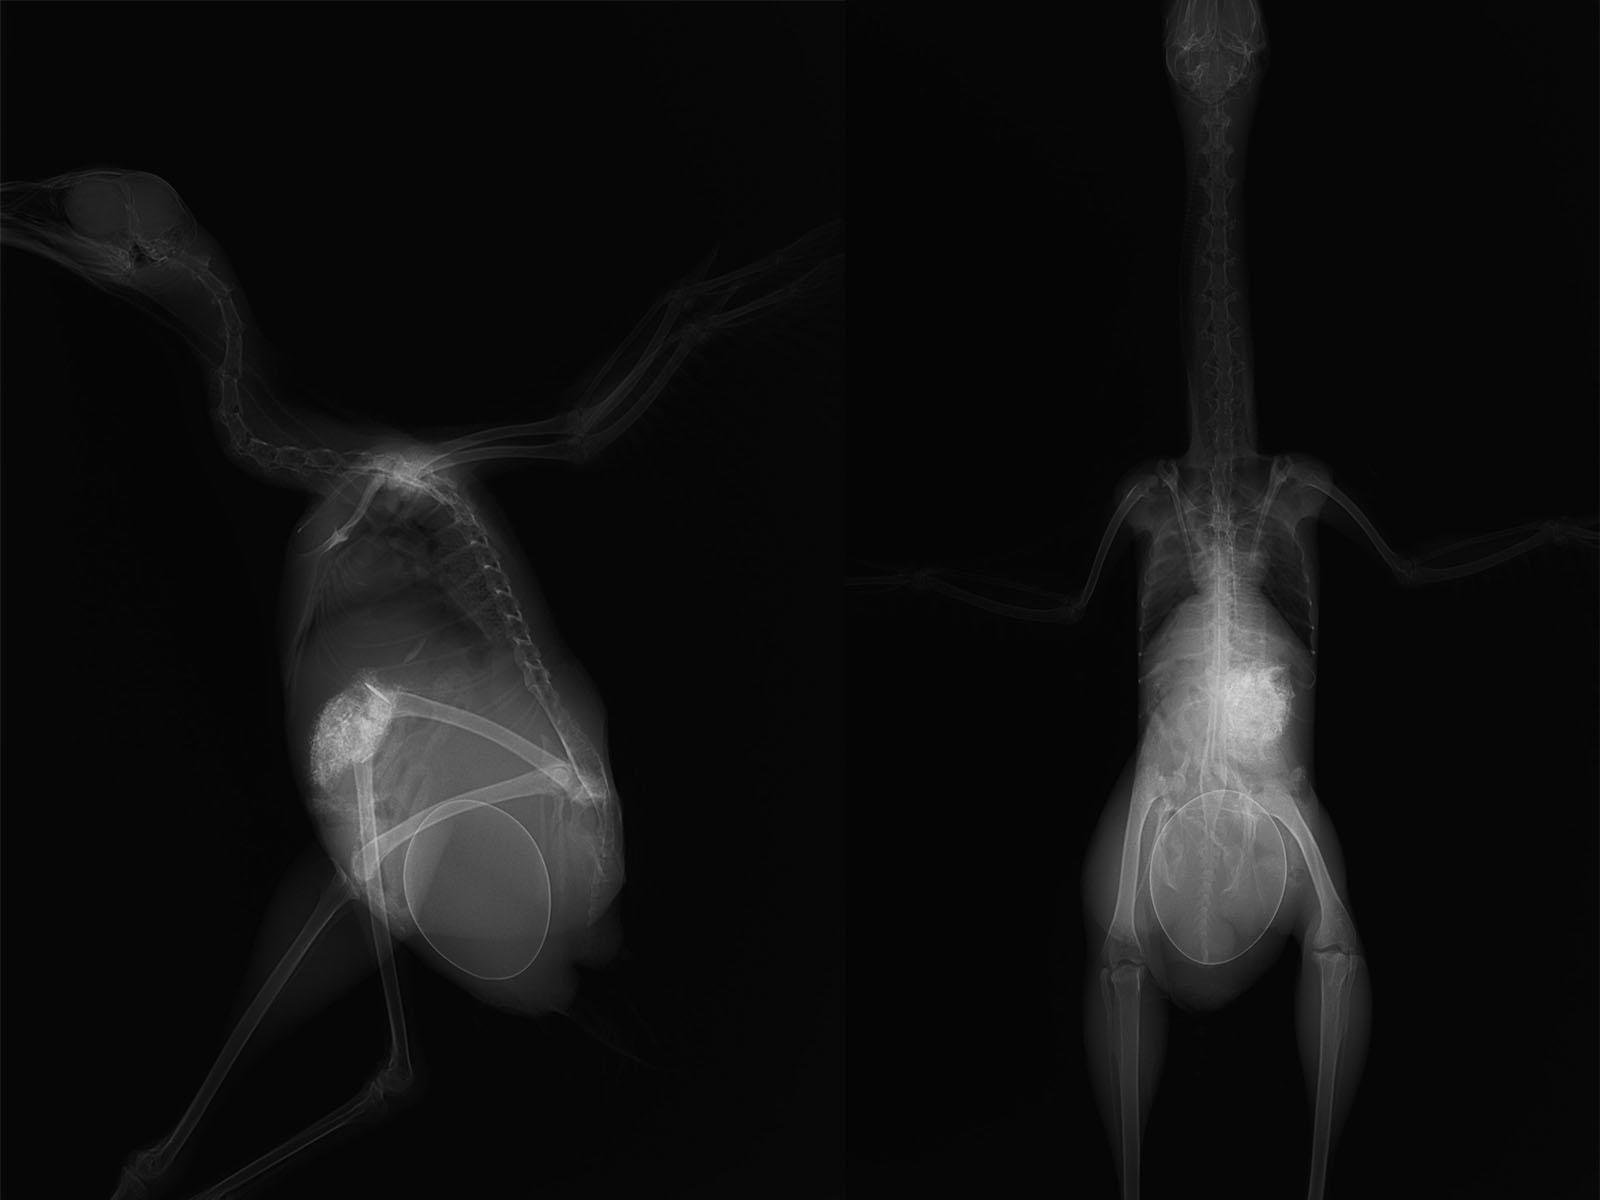

力なく横たわる瀕死の重傷を負ったヤンバルクイナに酸素吸入をしながらレントゲン検査や血液検査など終え、目に飛び込んできたのはヤンバルクイナのお腹の中の卵、そして、骨盤骨折。

レントゲンを見る限り、骨盤骨折するほどの衝撃を受けながら、お腹の中の卵は割れていません。

しかし、母鳥は卵を産む力は残っていませんでした。